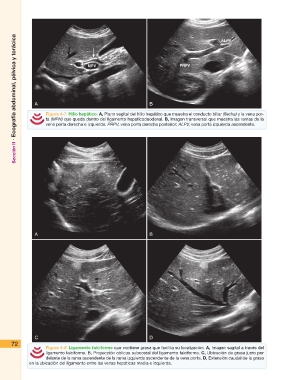

Figura 4-7 Hilio hepático. A, Plano sagital del hilio hepático que muestra el conducto biliar (flecha) y la vena por-

ta (MPH) que queda dentro del ligamento hepaticoduodenal. B, Imagen transversal que muestra las ramas de la

vena porta derecha e izquierda. PRPV, vena porta derecha posterior; ALPV, vena porta izquierda ascendente.

72 Figura 4-8 Ligamento falciforme que contiene grasa que facilita su localización. A, Imagen sagital a través del

ligamento falciforme. B, Proyección oblicua subcostal del ligamento falciforme. C, Ubicación de grasa justo por

delante de la rama ascendente de la rama izquierda ascendente de la vena porta. D, Extensión caudal de la grasa

en la ubicación del ligamento entre las venas hepáticas media e izquierda.